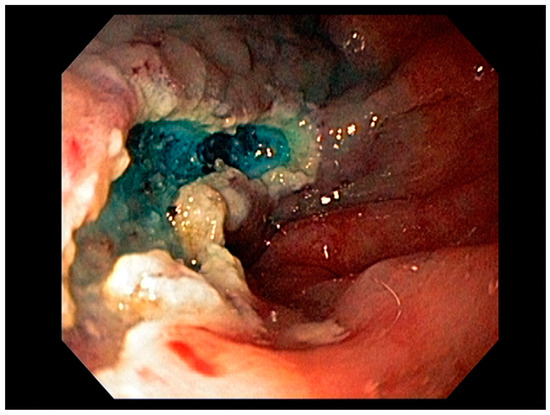

3.1. Endoscopic Therapeutic Options for Barrett’s Esophagus Associated Dysplasia

3.2. Endoscopic Resection Techniques for Early-Stage Esophageal Cancer (T1a and T1b)

- Waddingham, W.; Nieuwenburg, S.A.V.; Carlson, S.; Rodriguez-Justo, M.; Spaander, M.; Kuipers, E.J.; Jansen, M.; Graham, D.G.; Banks, M. Recent advances in the detection and management of early gastric cancer and its precursors. Front. Gastroenterol. 2020. [Google Scholar] [CrossRef]